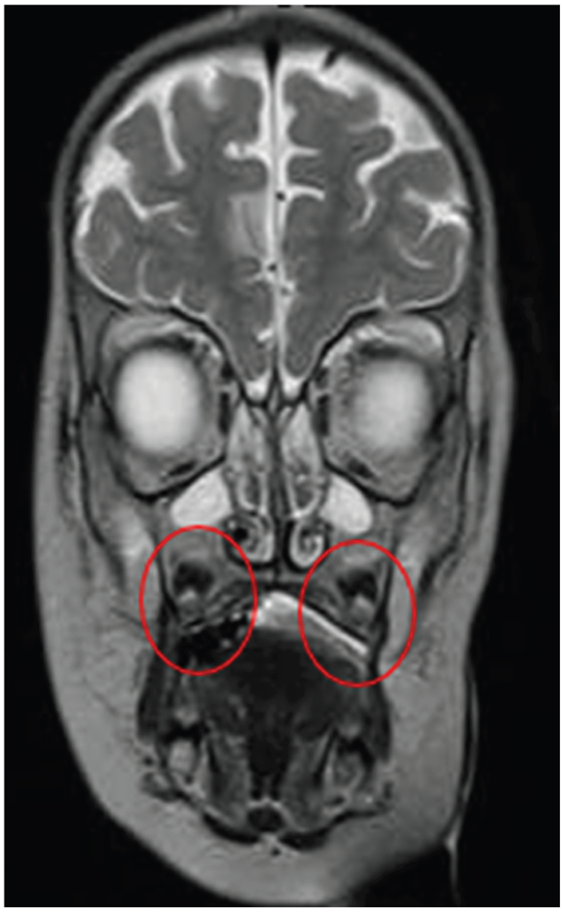

Quadrant D: T2 – FLAIR |

Abnormalities in gray-white matter differentiation are observed Hyperintense images are observed in the subcortical white matter – in the following regions: Bilateral occipital Bilateral parieto-occipital |

Quadrant E: T2 – FLAIR Hyperintense Tissue is Evident in Bilateral Maxillary SinusesConsistent with Sinusitis |